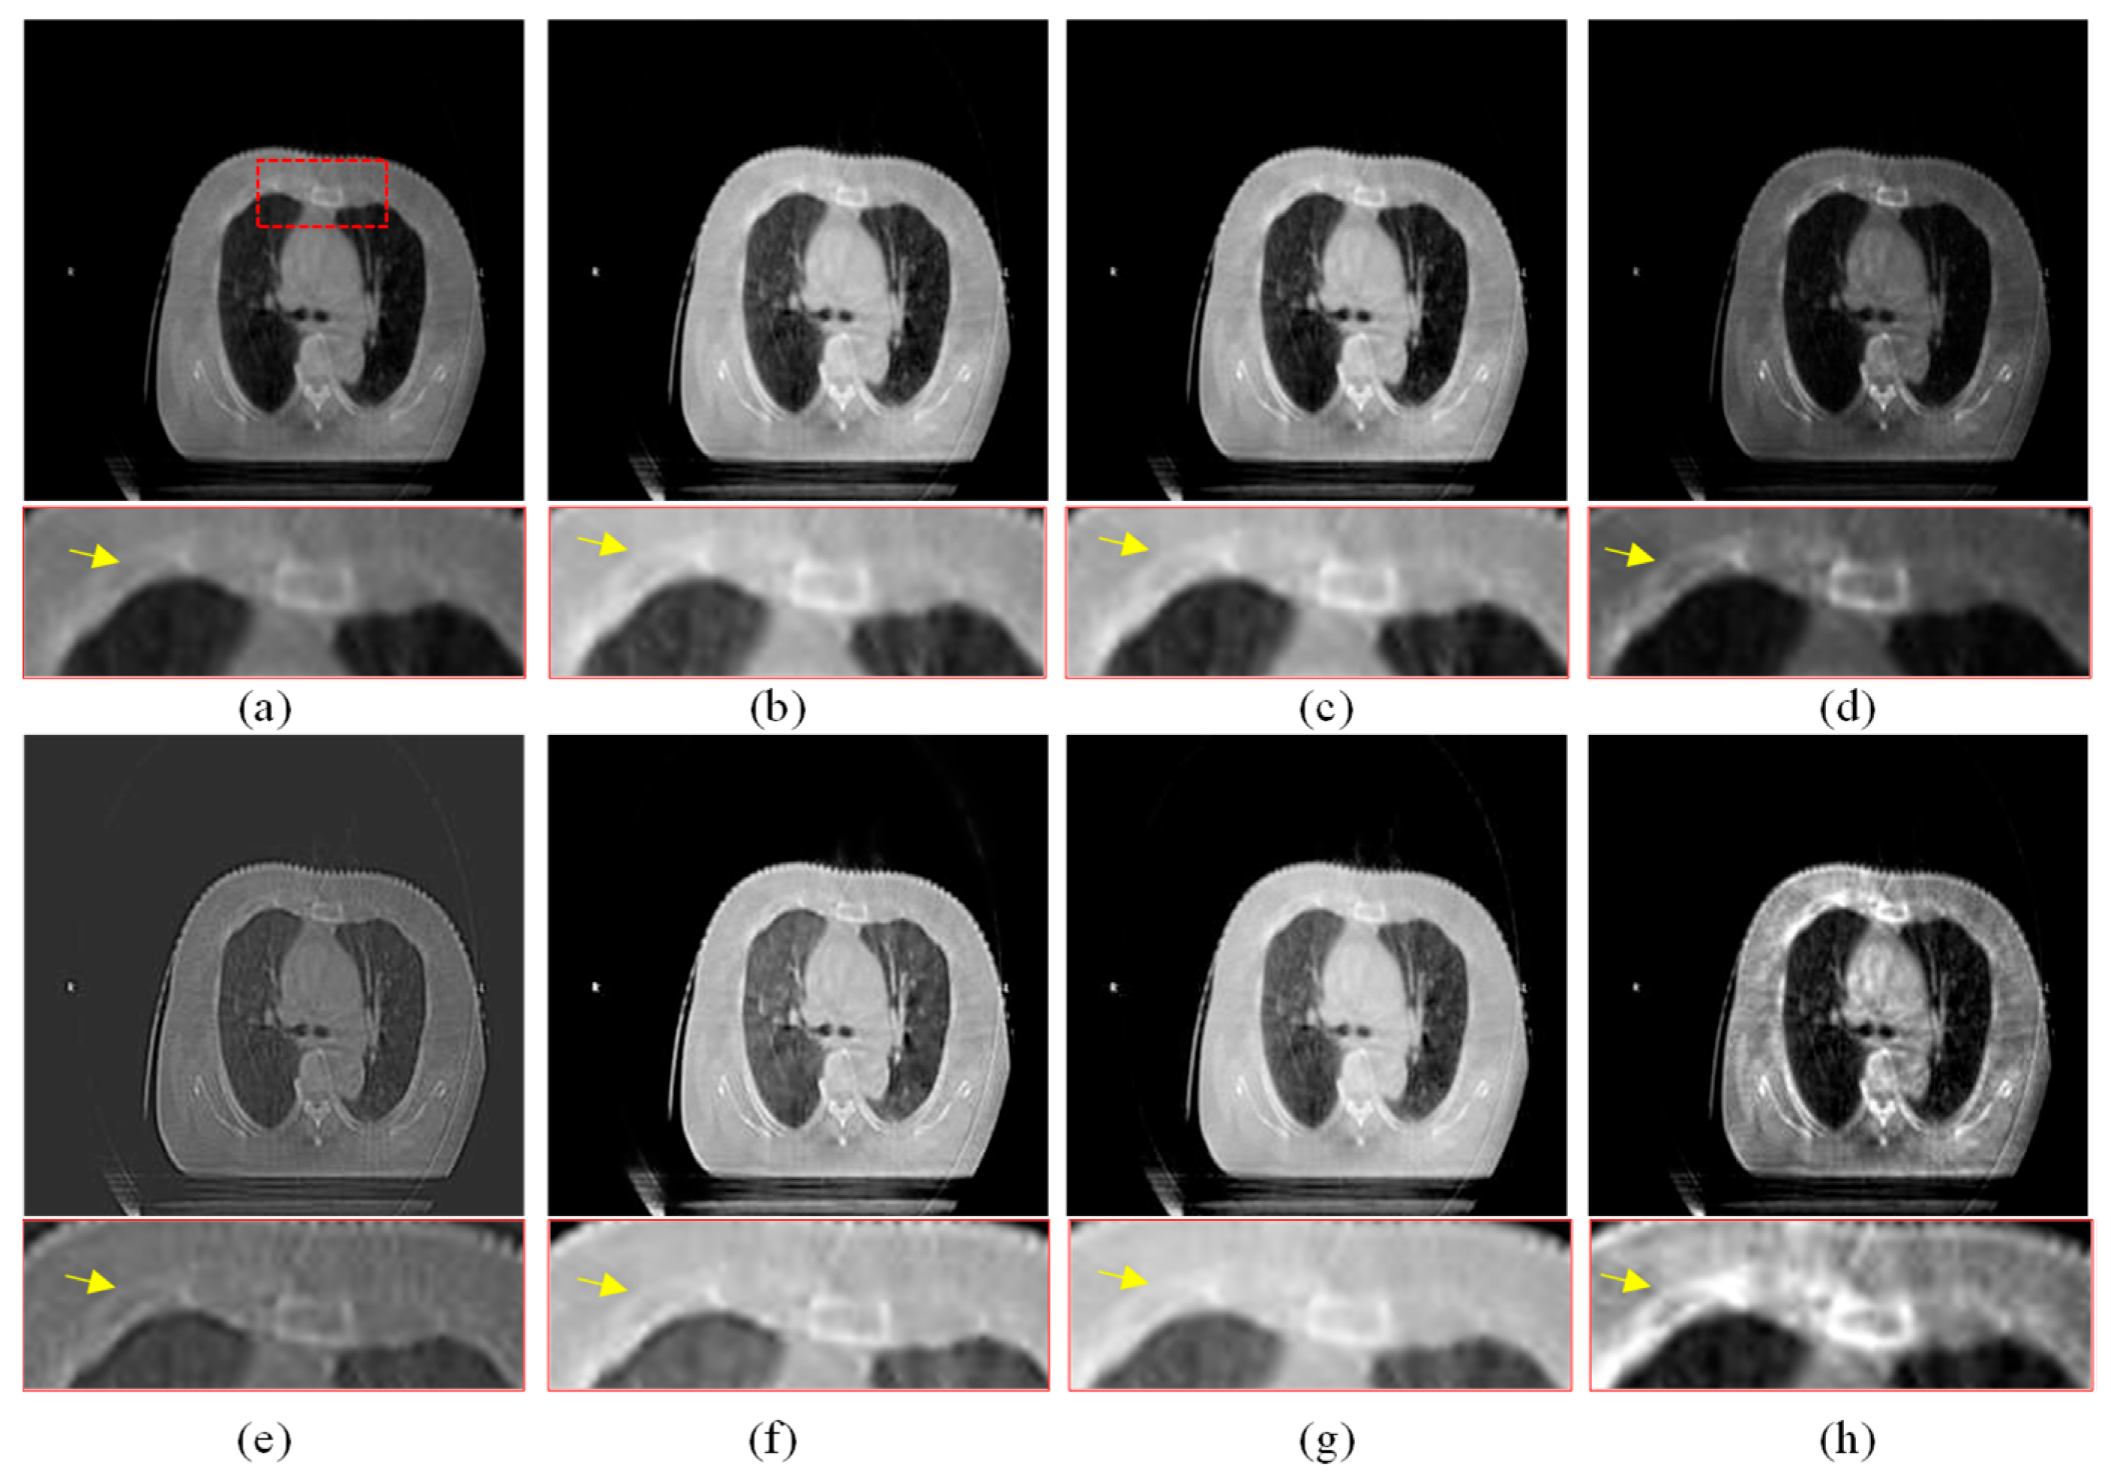

3.2. Subjective Comparison and Analysis

The visual comparison of different enhancement algorithms is shown in Figure 7, Figure 8, Figure 9 and Figure 10. Figure 7a is the source CBCT image, and Figure 7b is the image enhanced by MSR, which shows that the brightness of the source image is improved but with low contrast. Figure 7c,f,g show similar enhanced results with improved brightness but lacking in details. The DCP method improves the contrast of the source image, but does not enhance the details. As shown in Figure 7e, the CBF-based method shows good detail, but it still contains some noise. Compared with these methods, the proposed method shows better visual effects with higher contrast and richer detail, and the important regions are more significant.

Figure 7.

Enhanced results of pair 1. (a) Source CBCT images. (b) MSR. (c) MSRCR. (d) DCP. (e) CBF. (f) RRM. (g) SMIPC. (h) Ours.

Figure 8.

Enhanced results of pair 2. (a) Source CBCT images. (b) MSR. (c) MSRCR. (d) DCP. (e) CBF. (f) RRM. (g) SMIPC. (h) Ours.

Figure 9.

Enhanced results of pair 3. (a) Source CBCT images. (b) MSR. (c) MSRCR. (d) DCP. (e) CBF. (f) RRM. (g) SMIPC. (h) Ours.

Figure 10.

Enhanced results of pair 4. (a) Source CBCT images. (b) MSR. (c) MSRCR. (d) DCP. (e) CBF. (f) RRM. (g) SMIPC. (h) Ours.

Another three sets of experiments are shown in Figure 8, Figure 9 and Figure 10. As can be seen from the enlarged regions and the yellow arrows in Figure 8, it is difficult to directly observe the presence of skeletal information at this position from the enlarged region in Figure 8a. The enhancement results of the comparison methods also did not improve the visual contrast in this region, but the skeletal information can be clearly observed in our result, which means our results outperform the comparison algorithms in terms of detail, contrast, and visualization effect.

The same conclusion can also be obtained in Figure 9 and Figure 10. Especially in the enalrged region in Figure 10, our results provide a much clearer organizational structural and edge infromation, which is very helpful for disease diagnosis and treatment. Through comparison, it can be found that the rigidity informaiton in our results is more significant, the tissue edge in our results is clearer, and the contrast of the texture structure is also better than that of the comparison algorithms. The observation effect is greatly improved by our enhancement method, proving that our method can effectively enhance the CBCT images.